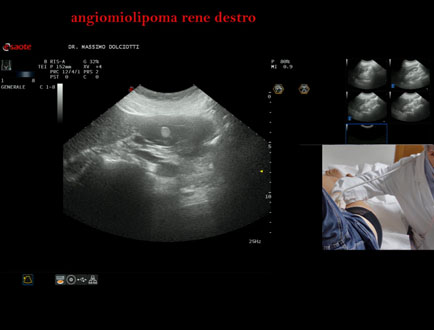

Motivazione dell'esame: follow up per angiomiolipoma renale destro

Commento all'esame: le immagini ed il video documentano al rene destro, in sede corticale polo inferiore, immagine iperecogena, a margini definiti, delle dimensioni di 25 x 23 mm, senza segni di vascolarizzazione, da ricondurre, come prima ipotesi, ad angiomiolipoma.

Conclusioni: angiomiolipoma del rene destro (angiomyolipoma of the right kidney).